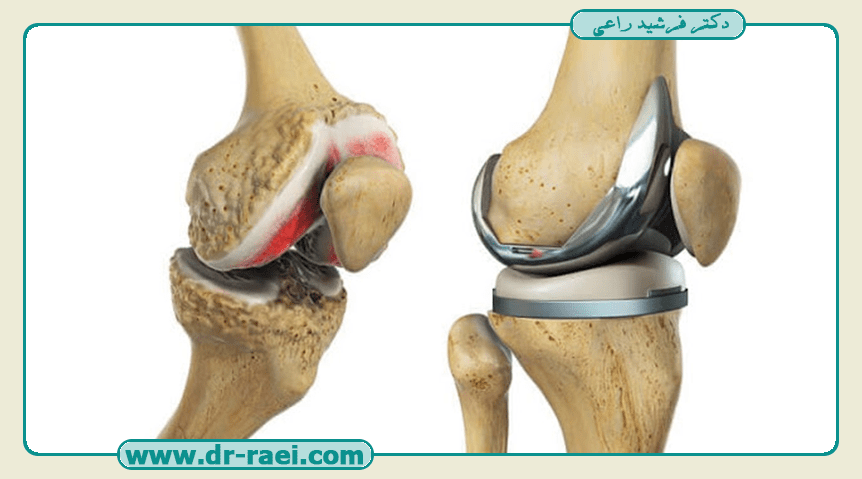

تمرینات بعد از عمل تعویض مفصل زانو

بعد از طی کردن دوران نقاهت پس از تعویض مفصل زانو و ترخیص از بیمارستان، متخصص فیزیوتراپ، بیمار را دقیق معاینه میکند و تمریناتی را برای شخص تجویز مینماید تا روند بهبودی بیمار به بهترین شکل انجام شود. در اینجا تمرینهای اصلی و مهم بعد از عمل، توضیح مختصری داده خواهد شد. دقت کنید که تمرینات را بهدرستی انجام دهید؛ زیرا برای بازگشت سلامتی شما بسیار حائز اهمیت خواهد بود.

با انجام حرکات صحیح و مشاوره با پزشک متخصص و فیزیوتراپیست میتوانید دوباره عضلات و مفاصل پای خود را به شرایط ایدهآل راهرفتن و حرکات روزمره برسانید. پشتکار شما و انجام درست و دقیق توصیههای پزشکی میتواند شما را هر چه سریعتر به شرایط مطلوب برساند و از سلامتی مجدد خود لذت ببرید.

با مراجعه به دکتر راعی متخصص ارتوپد در تهران، سلامت را دوباره در آغوش بکشید